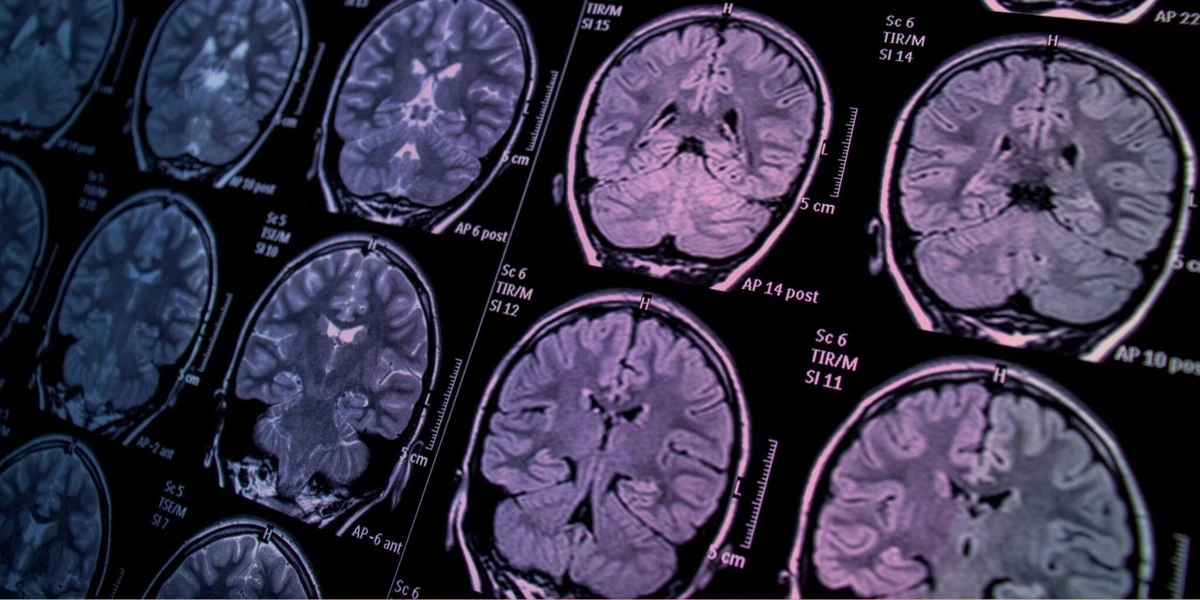

Jeśli kiedykolwiek zastanawiałeś się, dlaczego psylocybina czy LSD wywołują tak specyficzne efekty, odpowiedź leży w unikalnej aktywności neuronowej. Naukowcy wreszcie połączyli kropki, analizując ponad 500 skanów mózgu.

Zespół badaczy przeanalizował dane z 11 różnych projektów badawczych, obejmujących aż 267 osób. Co sprawdzano? Wpływ psylocybiny, LSD, meskaliny, DMT oraz ayahuaski na nasze centra dowodzenia.